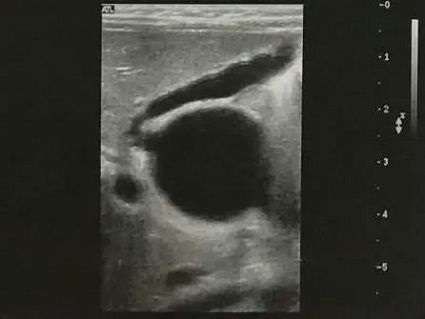

胆道闭锁患儿生后即出现黄疸、进行性加重、皮肤巩膜黄染、面色暗黄、大便淡黄色或白色陶土样等症状。由于新生儿胆总管纤细难以观察,因此通过以下胆囊形态变化判断是否胆道梗阻:胆囊大小正常但形态僵硬(图2),边缘不光整,长度可达2-3cm,内径大于0.4cm,可有小的憩室样结构形成;小胆囊,长度小于1-1.5cm,内径0.2cm,充盈差;胆囊小而且无充盈,仅可见胆囊痕迹,喂奶后无变化;以上三种胆囊均可合并有胆总管区囊肿,可与胆囊管及胆囊相通,但与肝左、右管不相通(见图3);小部分病例可见到肝内胆管局限性扩张(图4);病程后期(3个月以上),显示肝硬化改变(图5)。

▲ 图2 ▲ 图3